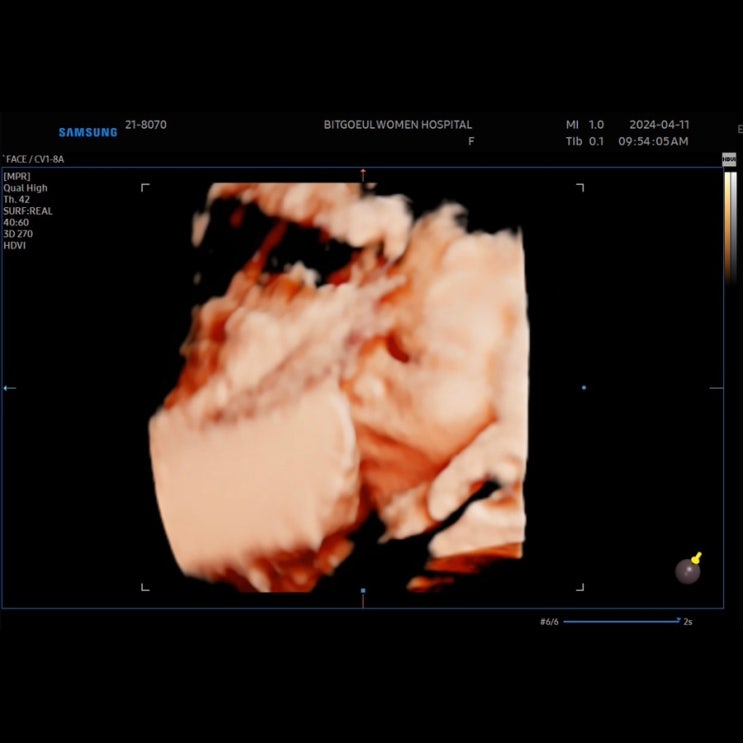

임신 31주차) 빛고을 여성병원 태동검사, 소요시간, 비용, 입체초음파

임신 31주차) 빛고을 여성병원 태동검사, 소요시간, 비용, 입체초음파 @드리미 30주차가 넘으면 태동이 장...